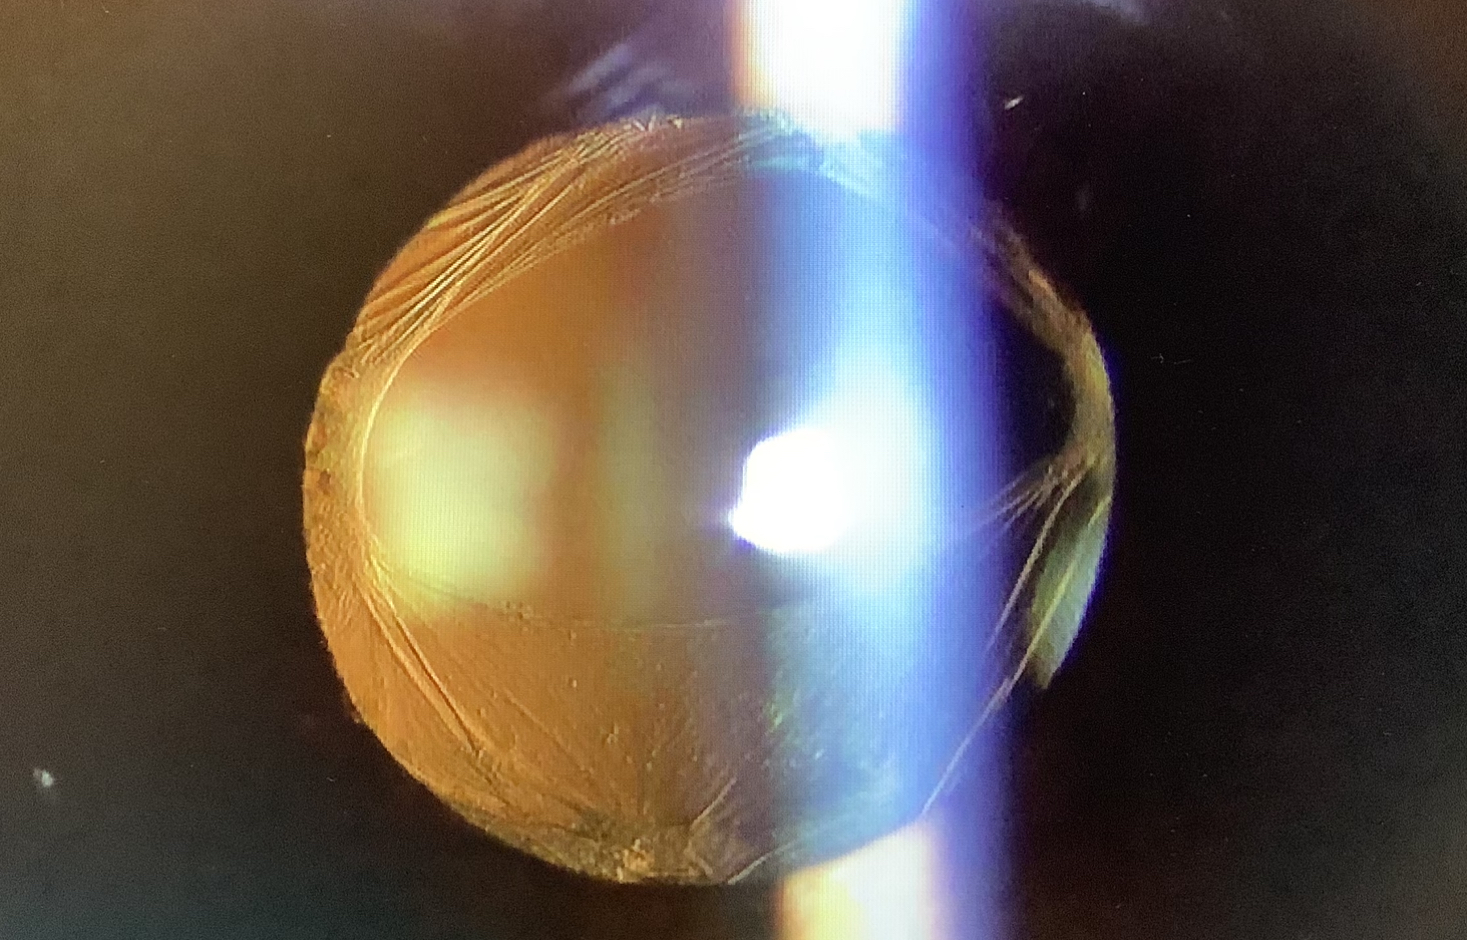

今日、外来受診された40代の男性の方は先月、他院で単焦点レンズで白内障の手術を受け、後嚢破損のため、レンズが落下してしまい、更に他の施設で硝子体手術を受けレンズを入れてもらったそうですが、術後からブレるような見え方が続き、『レンズが表裏逆に入っているのでは?』と心配されていらっしゃいました。

この患者さんの症状から、レンズがズレて入っているのかと疑って診させていただきましたが、レンズもきれいに入っており、表裏も正常でした。ただ、3.5Dほどの乱視があり、そのせいで出ている症状かと思われました。後嚢破損後は嚢外固定というレンズの入れ方をしなければならず、乱視矯正用のレンズ(トーリックレンズ)が使えないので、乱視が残るのはやむを得ない面があり、あとは眼鏡やコンタクトレンズでの矯正が必要になります。